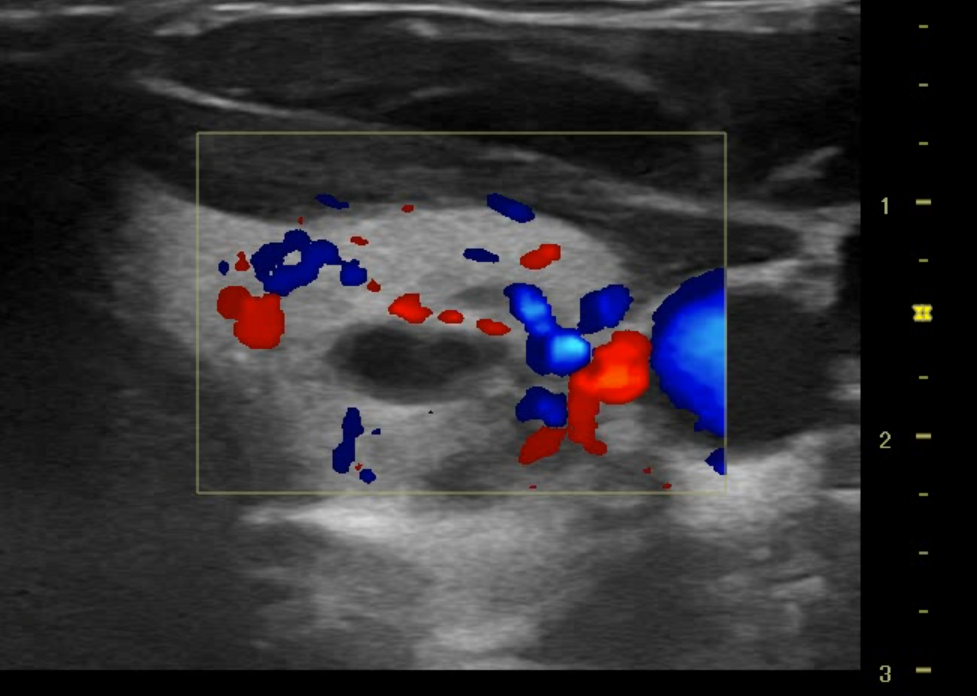

Se realizó ecografía en servicio de urgencias el cual encontramos los siguientes hallazgos:

Nódulo en polo inferior de lóbulo izquierdo de aproximadamente 2.08 X 1.47 x 3.63 cm de características de morfologías: con longitud mas alto que ancho, se observa trabéculas heterogéneas, visualizacion de leve vascularización sin evidencias de adenopatías colindantes, no se aprecia efecto masa en estructuras colindantes.